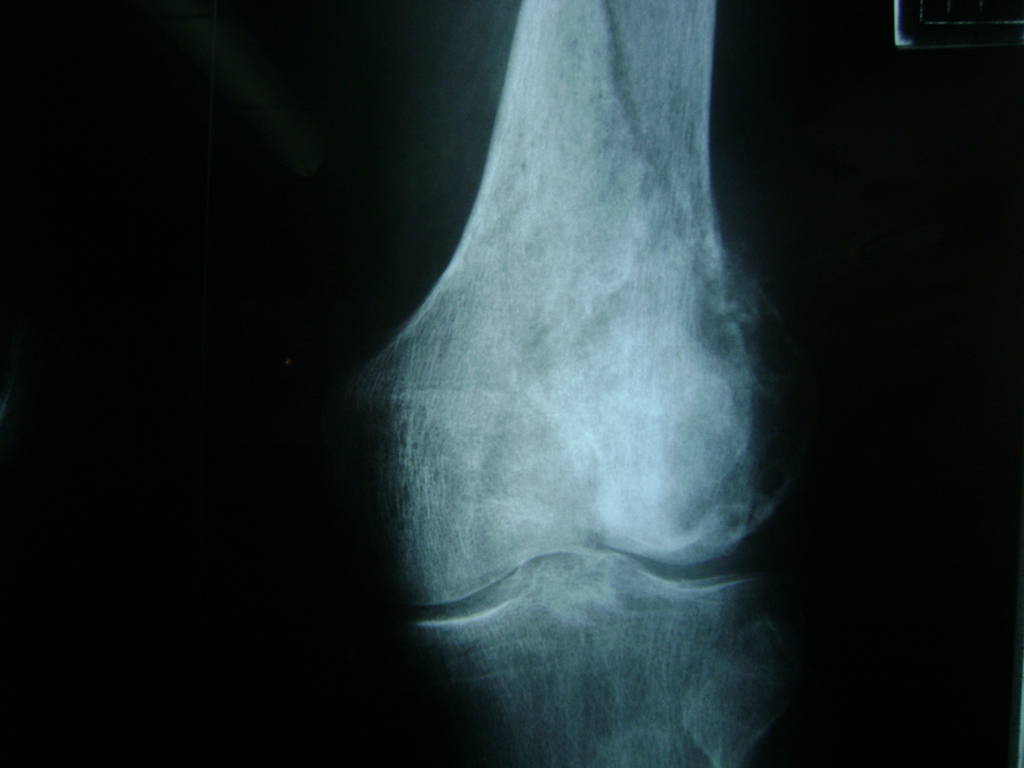

Fémur - Rodilla